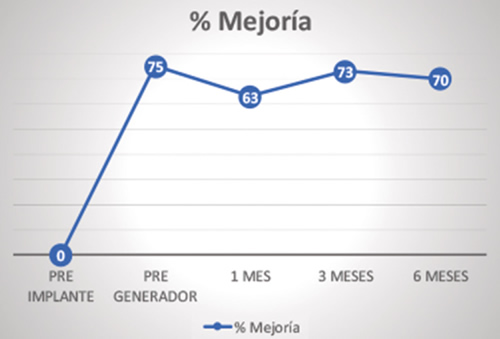

El porcentaje de mejoría subjetiva reflejado en los cuatro tiempos tras el implante del electrodo fue: 75,6 % ± 19,9 % a las 2 semanas, 72,5 % ± 24,3 % a 1 mes, 73,8 % ± 17,7 % a 3 meses y 70,6 % ± 14,3 % a 6 meses (Figura 6). Todos los pacientes que superaron la fase de prueba mantuvieron al menos una mejoría del 50 % a los 6 meses de tratamiento.

Fig. 6. Porcentaje de mejoría subjetiva percibida